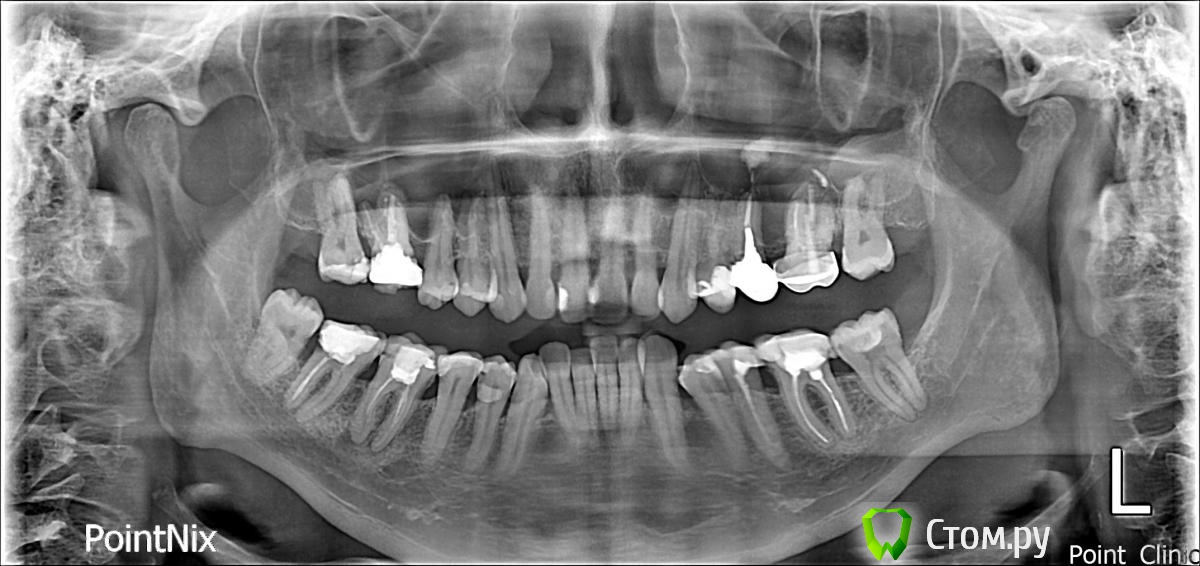

Гуля-Р Опубликовано 1 ноября, 2014 Поделиться Опубликовано 1 ноября, 2014 Добрый день! Ортодонт настаивает на удалении нижних центральных резцов, а не четверок, т.к. для корни нижних резцов подвержены резорбции. Если удалить четверки, то центральные резцы потом расшатаются и надо будет ставить импланты. Удаление резцов приведет к нарушению дикции, да и вид нижних зубов - 2 резца и сразу клыки - не хочется. Как думаете, есть ли шанс, что не потеряю резцы? Пока настроена на удаление четверок, но еще не могу решить. Когда я спросила, тогда расшатаются все 4 нижних резца, ведь корни с резобцией у всех этих резцов, ортодонт ответил, что 2 других резца будут двигать очень медленно и сохранят зубы. Может все 4 резца можно медленно раздвинуть... а потом как-то закрепить ... типа шинирования... Очень нужен совет, извелась вся. Ссылка на комментарий

Force Опубликовано 3 ноября, 2014 Поделиться Опубликовано 3 ноября, 2014 Центральные резцы не удаляются. Ортодонт ваш экстремал. Для комментариев нужны фото. http://forum.stom.ru/topic/4655-patcientam/Четверки на нижней челюсти удалять тоже не нужно. 1 Ссылка на комментарий

Фазлиев Азат Ильдусович Опубликовано 7 ноября, 2014 Поделиться Опубликовано 7 ноября, 2014 Улыбнуться на 6 зубов не получилось, даже помогая пальцами.Внизу вообще без удаления! Только сепарация по необходимости. Ссылка на комментарий

Гуля-Р Опубликовано 9 ноября, 2014 Автор Поделиться Опубликовано 9 ноября, 2014 (изменено) Ну все... нижние центральные резцы отстояла под расписку о том, что в курсе о резорбции и последствиях, удалили нижние четверки, теперь мои скученные зубы долны поместиться в ряд, тем более что удалила внизу единственную восьмерку. Надеюсь не испугаюсь в дальнейшем хирургического вмешательства. В любом случае, зубы должны стать ровнее. Спасибо за ответы. Они помогли мне сделать выбор и не удалить резцы. Изменено 9 ноября, 2014 пользователем Гуля-Р Ссылка на комментарий